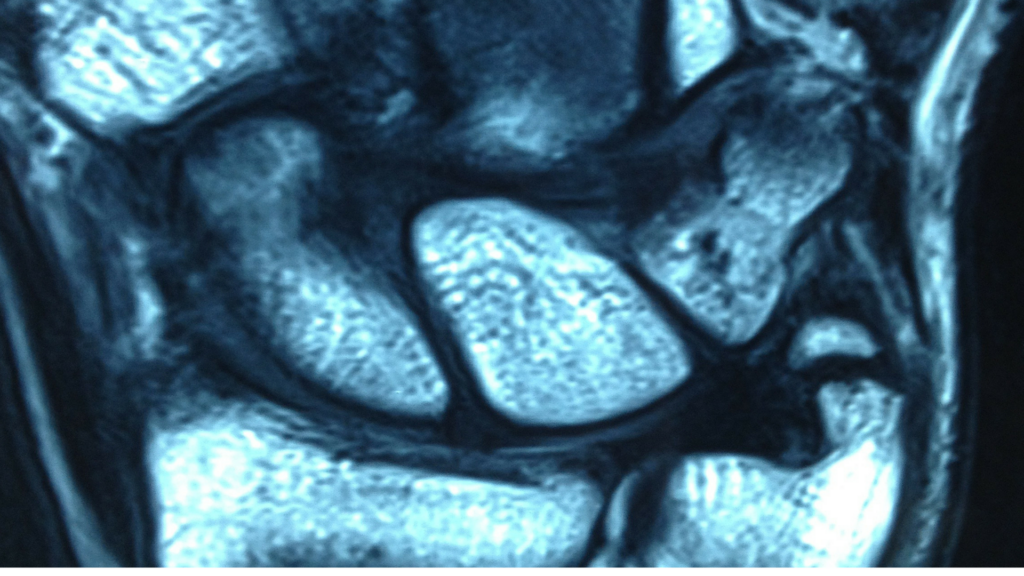

IMAGING

Suggest X-ray, MRI

A scapholunate ligament injury is one of the most common injuries in the wrist. It often occurs as a result of a repetitive or forceful push back of the wrist. This may happen from a fall on an outstretched hand, a gym accident while doing a bench press or a yoga move like a downward dog. It can sometimes be called “yoga wrist”. The scapholunate ligament connects the scaphoid to the lunate (2 small bones in your hand) and abnormal flexing or extension can cause a tear or strain because the scapholunate ligament connects these bones tightly.

No generally Scapholunate Ligament Injury does not require surgery. Hand Therapists at Action Rehab Hand Therapy Clinic can assess the X-ray or MRI and can advise if your Scapholunate Ligament Injury needs surgery.